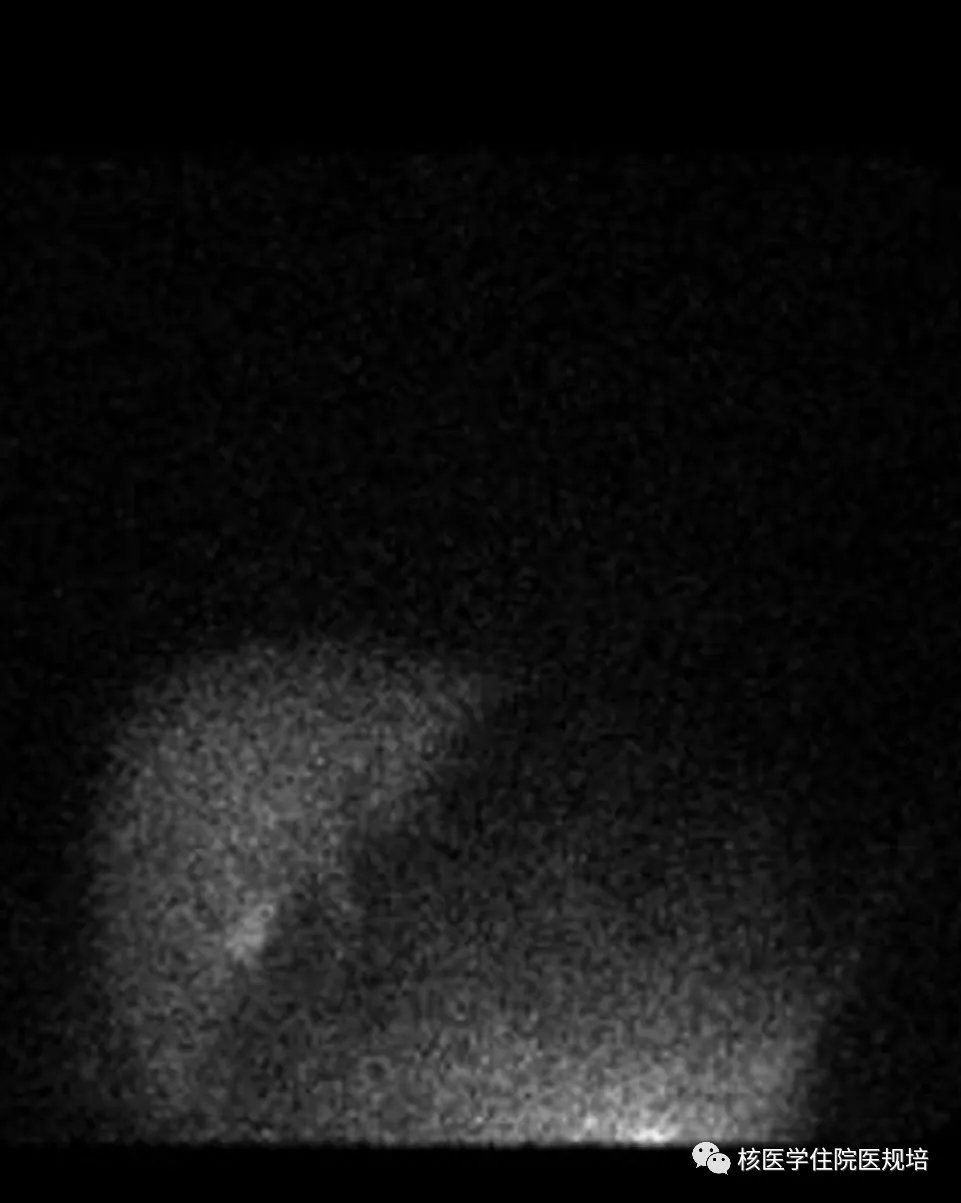

核素心/肝血流比值测定法的原理:直肠内注入99mTc-MIBI后被直肠粘膜吸收后,正常情况下通过直肠上静脉至肠系膜下静脉进入门静脉而运行至肝脏,被肝脏处理之后再经肝静脉汇入下腔静脉,因此99mTc-MIBI绝大部分首先被肝脏摄取,肝脏显影清晰,而心影不显影或显影浅淡(图2)。当门静脉压力增高时,由于位于直肠下段粘膜下层的吻合支,即直肠静脉丛开放,使部分显像剂绕过肝脏而直接回心,从而使心脏较早的显影清晰,心肌摄取显像剂明显增高(图1),且对显像剂的摄取量与分流程度成正比。

/肝血流比测定正常影像